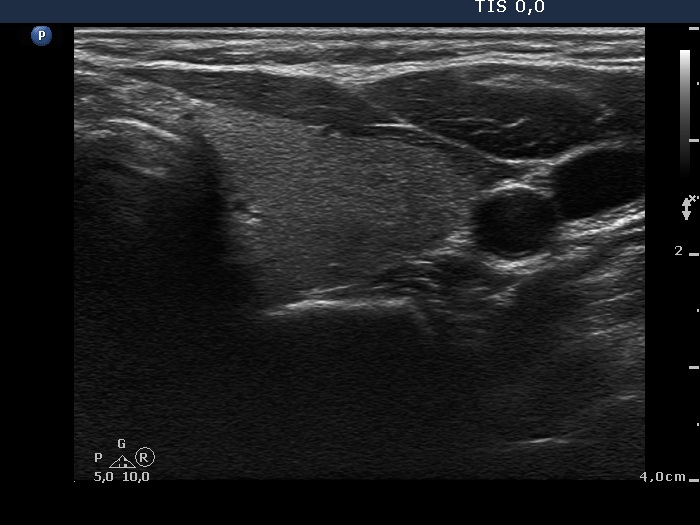

Subacute granulomatous thyroiditis - case 1777

Five months after the first examination (ultrasonographic picture 6)

Right lobe, longitudinal scan